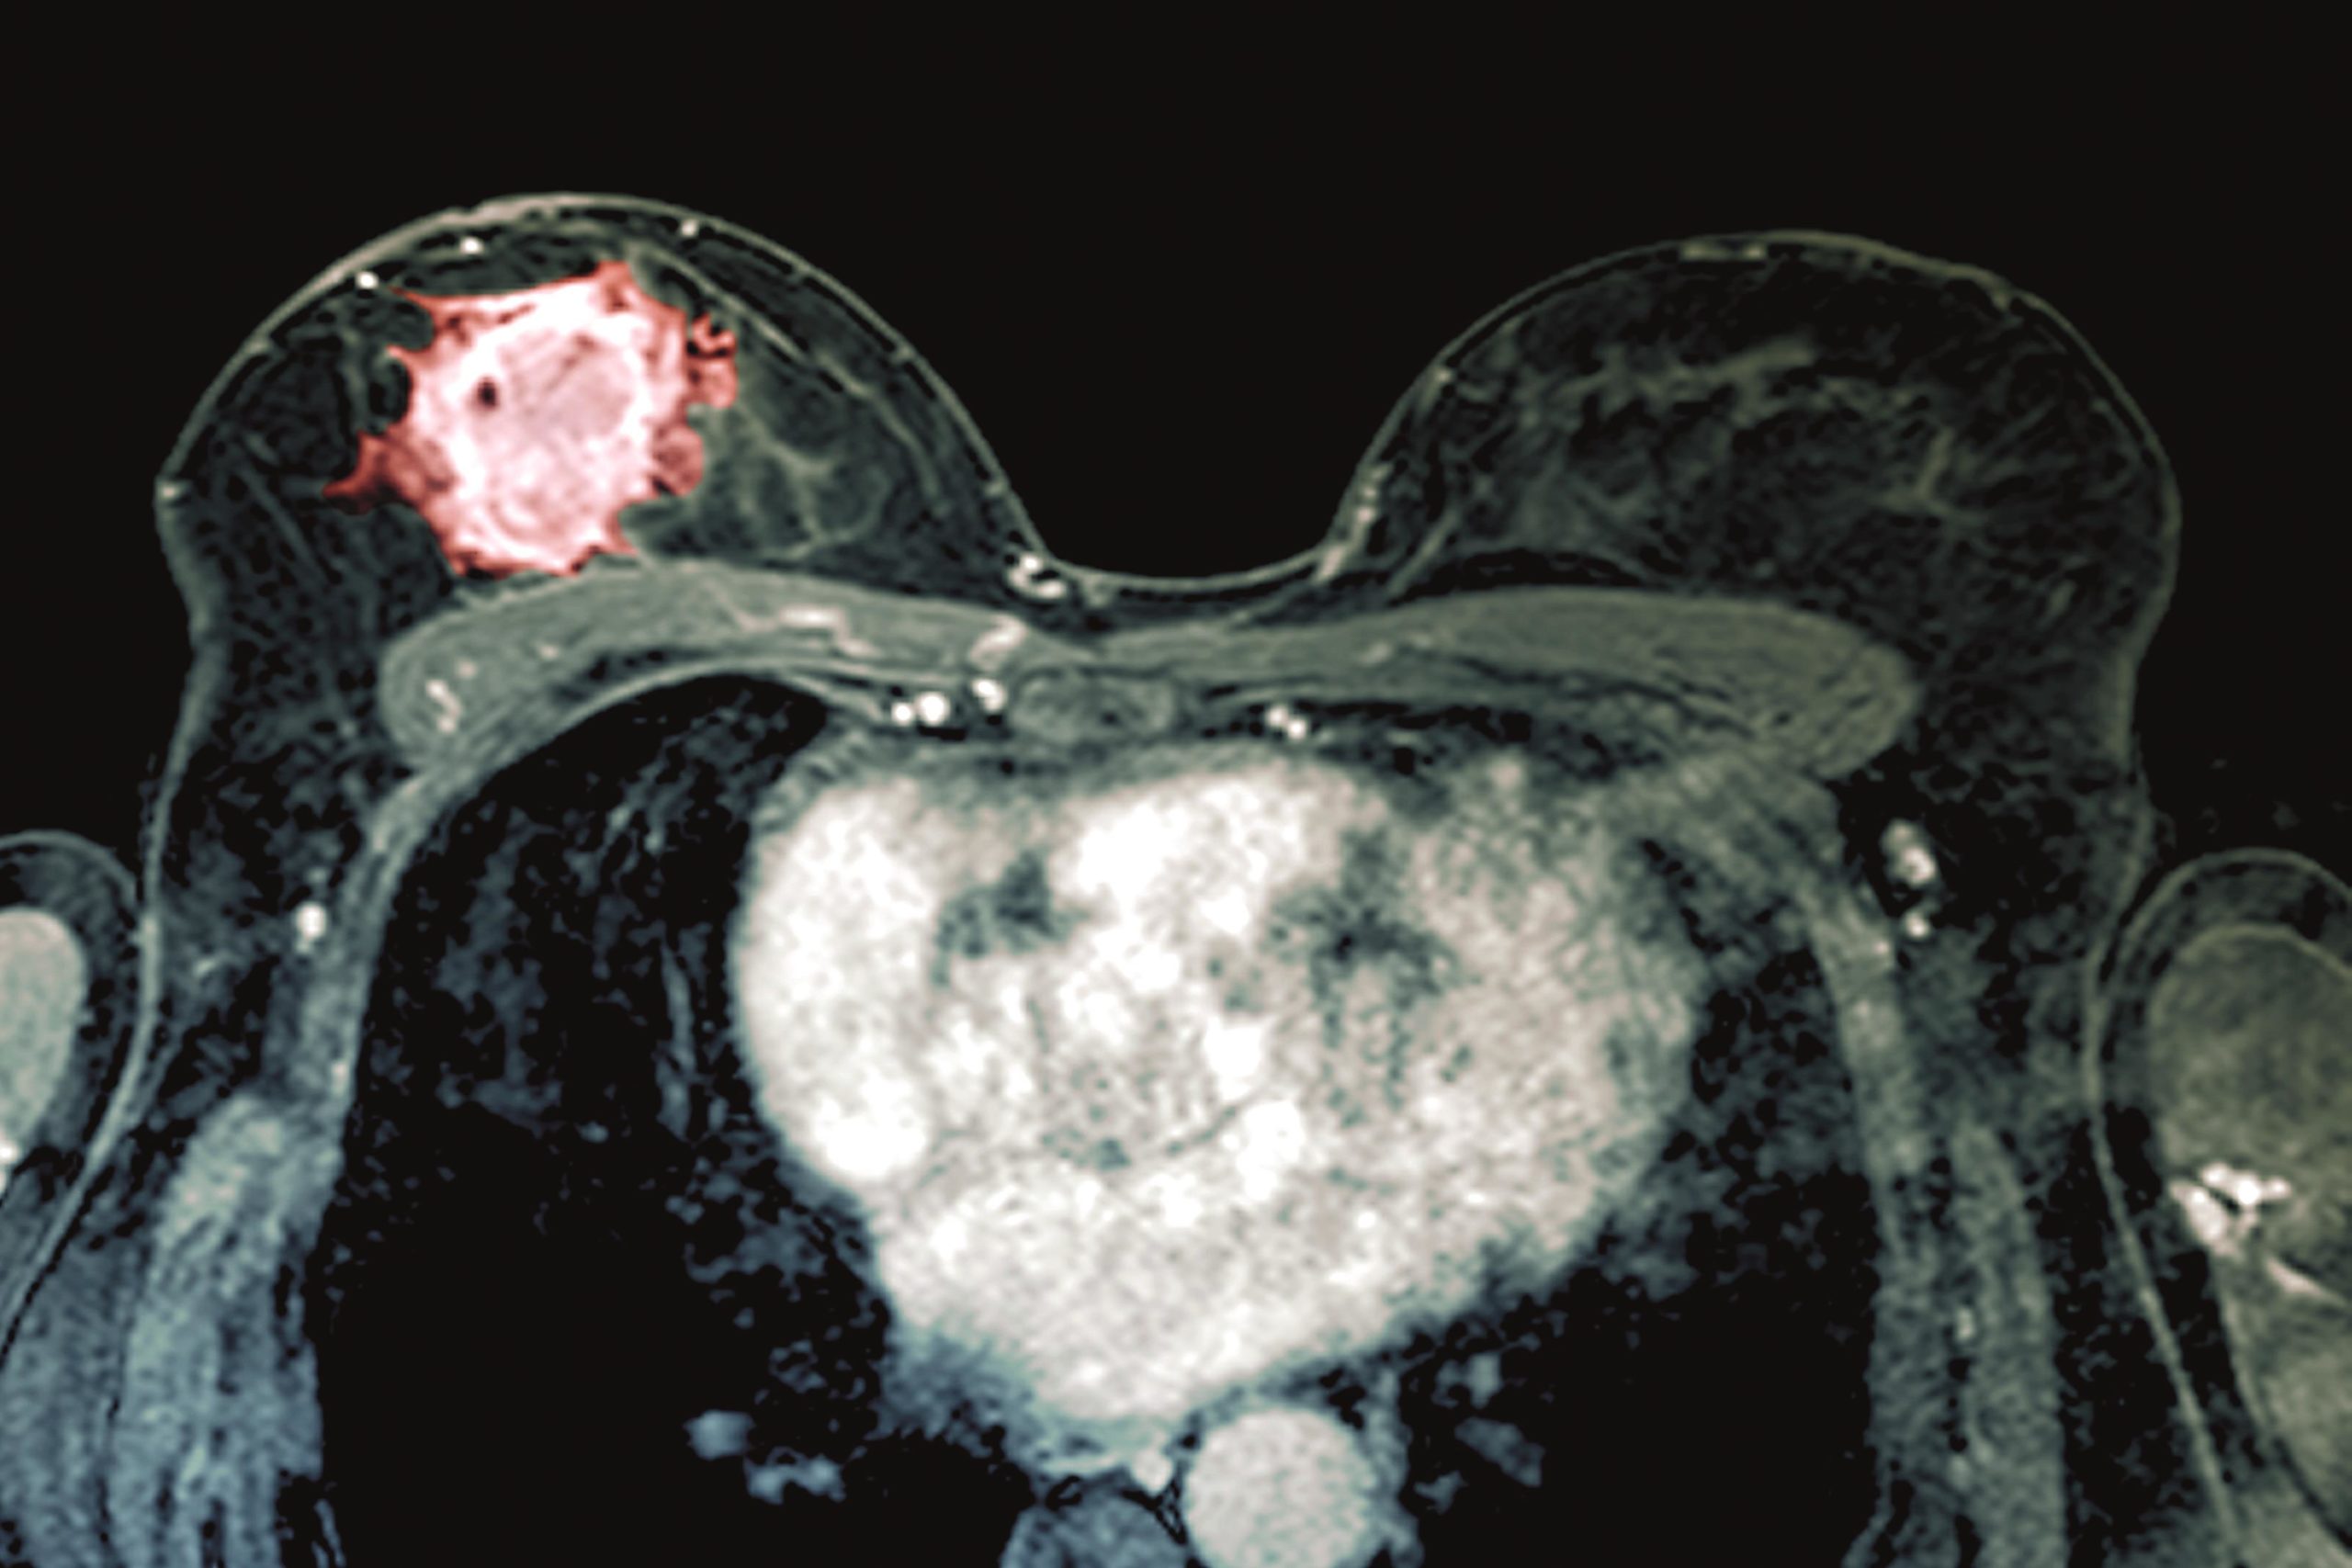

Is Against Breast Cancer A Genuine Charity - Breast Cancer Is Important But So Are Other Cancers / Most breast cancers are sporadic, meaning they develop from damage to a person's genes that occurs by chance after they are born.. The latest cancer incidence age statistics for the uk for health professionals. Left unchecked, malignant cells eventually can spread beyond the original tumor to other parts of the body. This study dwells on the buffer theory, which reflects the belief that support buffers against the adverse effects of stressors under conditions of high stress. Against breast cancer fund research into secondary spread, the main cause breast cancer related deaths. In some cases, cancerous cells can invade surrounding breast tissue.

Footage from a recent spinathon fundraiser, a 3 hour team relay held to raise funds for breast cancer research.participants could spin for as much, or. Against breast cancer is the story of the personal crusade of our founders dr anthony leathem and his wife patricia in their quest for a future free of today, against breast cancer funds pioneering research into new treatments, tools for earlier diagnosis and advice to reduce the risk of recurrence. National breast cancer awareness month represents an opportunity for all americans to devote some time to offering their support to the millions of women below, we've put together links to seven breast cancer awareness charities that are most deserving of your support, but before that, let's go over a. The latest cancer incidence age statistics for the uk for health professionals. The goal of against breast cancer is to prevent secondary spread, the main cause of breast cancer related deaths.

We fund groundbreaking research to improve detection, treatment and increase survival after breast cancer diagnosis. The bras are weighed and money per kilo given to the breast friend charity. Breast cancer is a disease in which certain cells in the breast become abnormal and multiply uncontrollably to form a tumor. Hpv and hepatitis b vaccines can help prevent cancer. Without looking at the genes of an affected relative first, testing a healthy individual would be like reading through an entire.

Breast Cancer Surf Etsy from i.etsystatic.com Our vision is a future free from breast cancer. In some cases, cancerous cells can invade surrounding breast tissue. Against breast cancer is the story of the personal crusade of our founders dr anthony leathem and his wife patricia in their quest for a future free of today, against breast cancer funds pioneering research into new treatments, tools for earlier diagnosis and advice to reduce the risk of recurrence. The risk goes up for women with certain types of benign breast lumps and for. Exercise seems to protect against breast cancer in several ways. Against breast cancer are working to prevent secondary breast cancer by funding unique research into 3 main areas Inherited breast cancer occurs when gene changes called mutations are passed down within a family from parent to child. Some cancers are caused by human papillomavirus (hpv), a very common sexually transmitted infection.